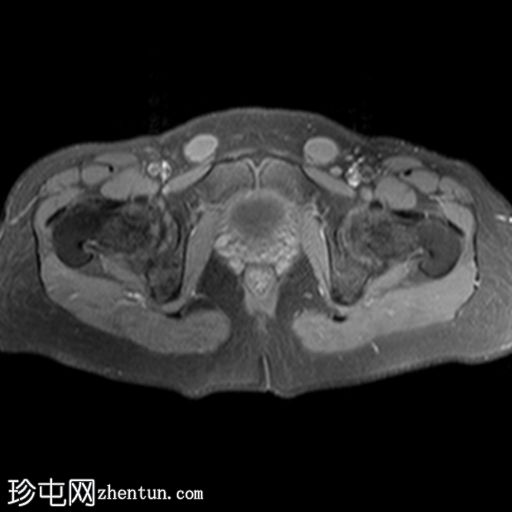

轴位

T2加权像

子宫缺失

卵巢缺失

阴道下三分之一发育不全,上三分之二缺失

可见双侧腹股沟卵圆形结构,提示隐睾(右侧约2.4×2厘米,左侧约2.3×2厘米)

上述特征符合雄激素不敏感综合征(睾丸女性化综合征)的典型表现。

核型分析显示46XY染色体。